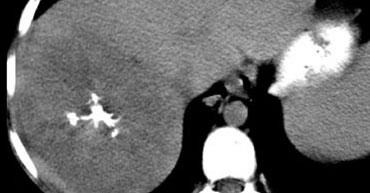

U máu gan trên CT không tiêm thuốc, thì động mạch muộn, thì tĩnh mạch cửa muộn và thì cân bằng. Lưu ý tỷ trọng của u máu tương đương với hồ máu trong tất cả các thì (mũi tên).

Hồ máu và U máu gan

Thông thường khi đánh giá các tổn thương ngấm thuốc, tỷ trọng của tổn thương luôn được so sánh với tỷ trọng của nhu mô gan.

Tuy nhiên, đối với u máu gan, không nên so sánh tỷ trọng của tổn thương với gan mà phải so sánh với hồ máu.

Điều này có nghĩa là các vùng ngấm thuốc trong u máu phải tương đương với tỷ trọng của các mạch máu tương ứng (hồ máu) ở mọi thời điểm.

Vì vậy, trong thì động mạch, các phần ngấm thuốc của tổn thương phải có giá trị tỷ trọng gần bằng với động mạch chủ đang ngấm thuốc, trong khi ở thì tĩnh mạch cửa phải tương đương với sự ngấm thuốc của tĩnh mạch cửa.

Nếu tỷ trọng không tương đương với hồ máu trong tất cả các thì tiêm thuốc, hãy loại bỏ chẩn đoán u máu gan.

Hình bên trái là một u máu gan điển hình.

Lưu ý rằng trên CT không tiêm thuốc, tỷ trọng của khối u tương đương với tỷ trọng của các mạch máu.

Trong thì động mạch, tỷ trọng tương đương với hồ máu và gần bằng với động mạch chủ.

Trong thì tĩnh mạch cửa, tỷ trọng tương đương với tĩnh mạch cửa.

Trong thì cân bằng, tỷ trọng ngấm thuốc tương đương với các mạch máu.

Cuối cùng tổn thương sẽ trở nên đồng tỷ trọng với gan, nhưng chỉ vì các mạch máu cũng trở nên đồng tỷ trọng với gan.

Điều này không liên quan đến tỷ trọng của bản thân nhu mô gan.

Vì vậy, hãy nghĩ đến hồ máu thay vì gan khi nghĩ đến u máu gan.